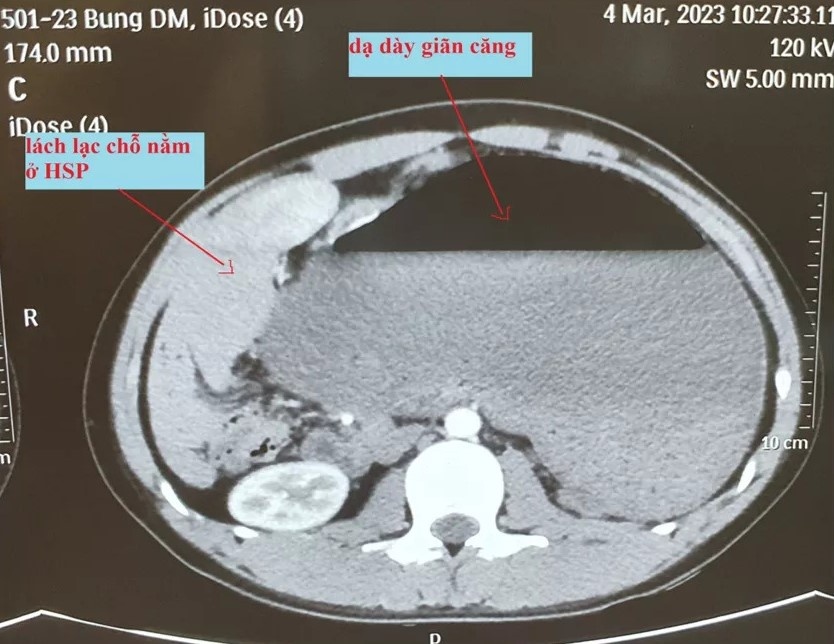

Đồng thời, hình ảnh cắt lớp vi tính cho thấy dạ dày giãn căng, lách lạc chỗ nằm vị trí hạ sườn phải ngay dưới gan, thận trái lạc chỗ nằm ở hố lách. Từ đó, bác sĩ chẩn đoán bệnh nhân bị xoắn dạ dày.

Hình ảnh cắt lớp vi tính của bệnh nhân. Ảnh: BVCC.